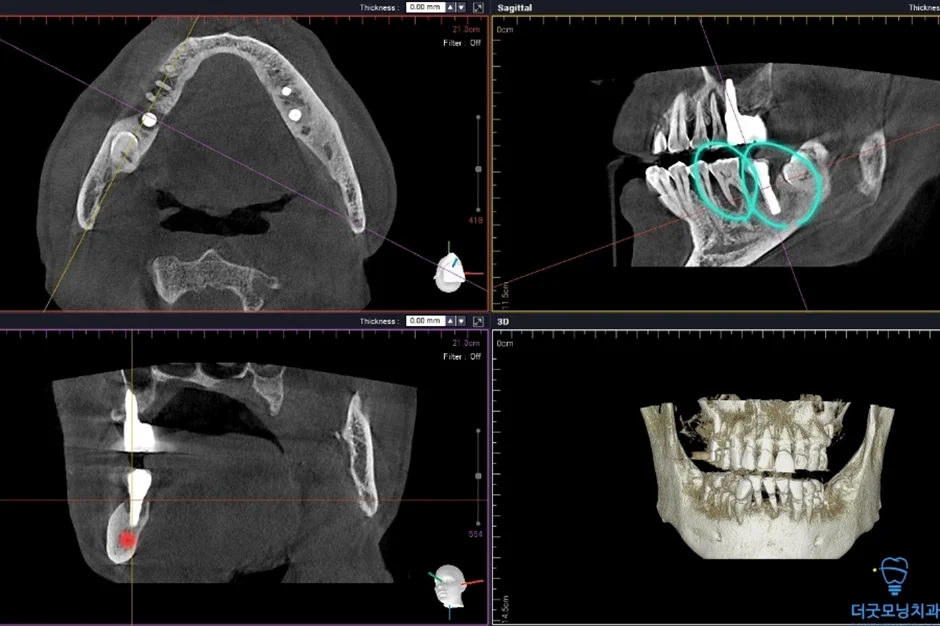

2. 검진 결과 — 파노라마 엑스레이 & CT 분석

먼저 파노라마 엑스레이와 CT를 통해 구강 전체 상태를 확인하였습니다.

■ 왼쪽 위 (상악 좌측)

상악동이 많이 함기화되어 있어 상악동 골이식(치조정 접근 상악동 거상술)이 반드시 필요한 상태였습니다. CT 확인 결과 가용골이 매우 부족한 것이 명확히 확인되었습니다.

임플란트 주위염이 발생하여 기존 임플란트를 제거하고 재수술이 필요한 상태였습니다. CT 상 신경관까지 어느 정도 거리가 확보되어 재수술은 무리 없이 진행 가능하였습니다.